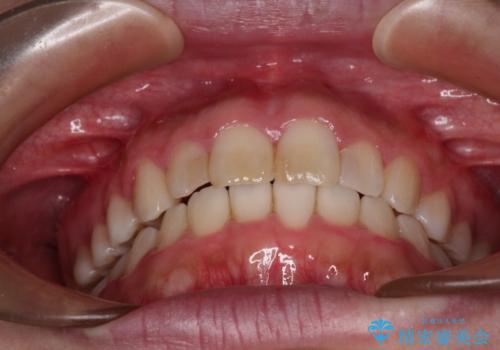

気になる前歯を治したい インビザラインで気づかれずに矯正治療

- ワイヤーではない矯正治療があると聞いたとのことで来院された患者様です。

長年前歯のデコボコを気にしていたもののワイヤー矯正に抵抗があり躊躇していたそうですが、インビザラインなら治療してみたいとのことで相談にいらっしゃいました。

インビザライン適用の歯列であったため、歯と歯の間を削るIPRを用いて改善することとしました。

お仕事柄、長時間のマウスピース装着が苦ではなかったので、歯列はすぐに整いましたが、ゆっくりとした交換頻度であったので、2年ほどの治療期間を要しました。